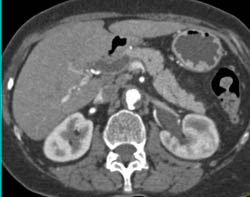

Bleed in and Near Liver S/p Stab Wound